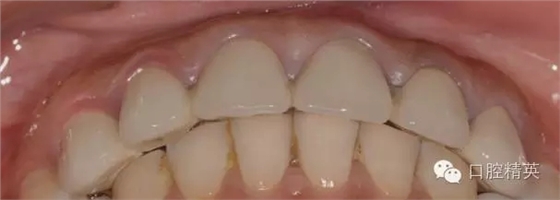

修復(fù)體完成口內(nèi)照片

640.webp (21).jpg